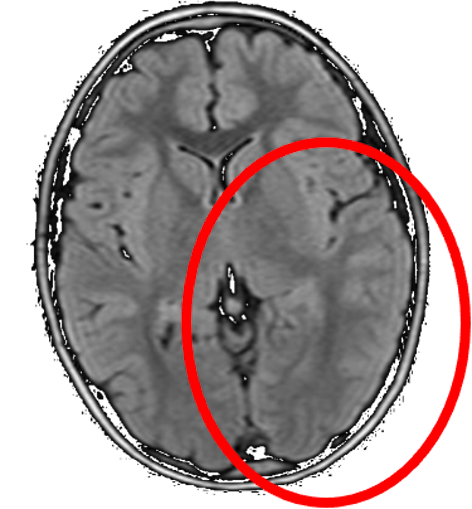

Viene eseguita TC encefalo in urgenza, da cui non emergono alterazioni densitometriche riferibili a lesioni acute. Agli esami ematochimici nulla di rilevante, a eccezione di lieve leucocitosi neutrofila associata a minimo rialzo della PCR. La consulenza oculistica rileva fundus oculi nella norma. Viene dunque avviata terapia infusionale di supporto e antibiotica. Dopo circa 12 ore si assiste a comparsa di deficit stenico dell’emilato destro e di cefalea di moderata intensità: si richiede pertanto RM encefalo che documenta lieve diffuso appianamento dei solchi corticali a livello dell’emisfero di sinistra associato a minimo rigonfiamento corticale, più evidente in regione temporale (Figura). Il tracciato EEG rileva un’attività di aspetto asimmetrico, costituita prevalentemente da ritmi lenti in assenza di elementi epilettiformi. Sulla base dei suddetti esami, viene intrapresa terapia antiedemigena steroidea con desametasone, associata a terapia anticomiziale con levetiracetam. Si assiste a un progressivo miglioramento clinico con risoluzione completa del deficit motorio, dell’afasia e con ripristino dell’integrità del sensorio a distanza di 48 ore. Durante il ricovero veniva inoltre effettuata puntura lombare, con esito nella norma.